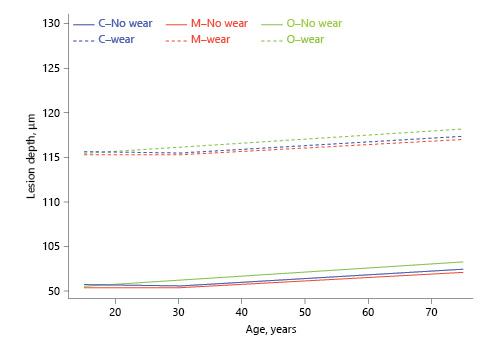

For LD, before the age of 30 years, only the slope for the occlusal third was significantly >0, indicating that under the age of 30 years, age had no effect on LD for the cervical or middle thirds. The slope before the age of 30 years was significantly higher for the occlusal than for the cervical third. After the age of 30 years, all 3 slopes were significantly >0 and not significantly different from each other (Table 1; Fig. 3).

Fig. 3

Association between estimated dental age and lesion depth (inflection point in the regression line at age 30 years, based on visual observation).

For LD, the cervical third was significantly larger than the middle third at the age of 15 and 75 years but not at 30 years. The occlusal third was significantly larger than middle and cervical thirds at the age of 30 and 75 years.